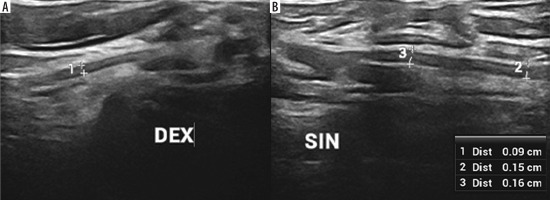

Figure 1

High-resolution ultrasound image of the suprascapular nerve torsion with a double “hourglass-like” constriction sign – marked with arrows (B) in 57-year-old patient with Parsonage-Turner syndrome in comparison with asymptomatic side (A). Images obtained by author with a 3-19 H linear probe of the Alpinion XCube90